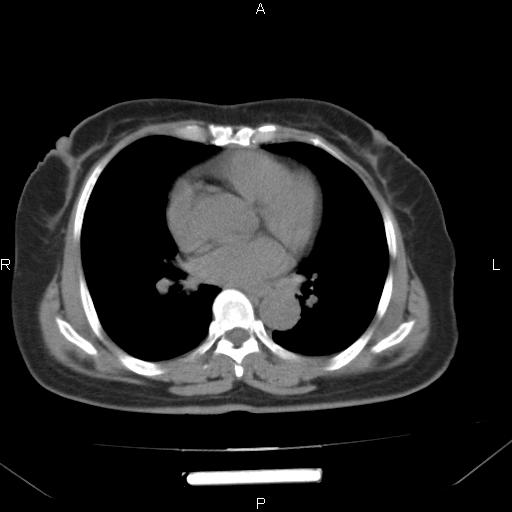

胸腺瘤

女、63Y 双眼睑下垂,早轻晚重。 胸腺瘤???

结果胸腺瘤